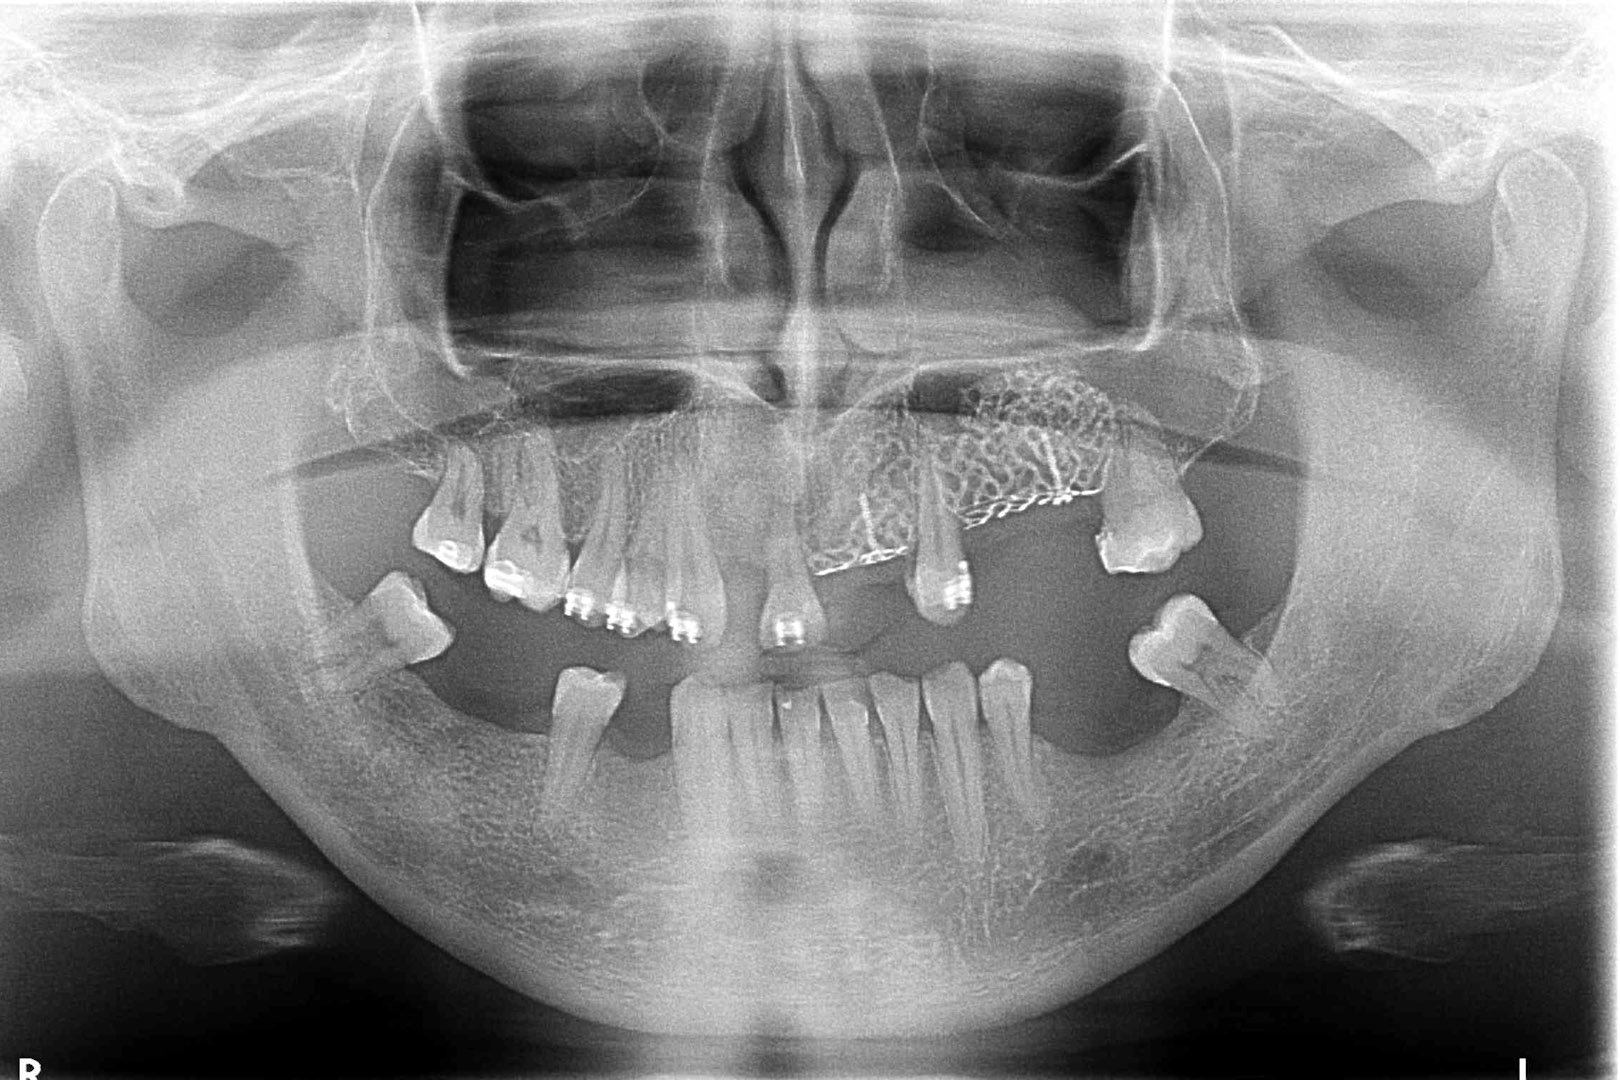

Przed podjęciem leczenia należy określić stopień zaniku kości szczęk oraz żuchwy. W tym celu przeprowadza się badanie kliniczne oraz odpowiednią diagnostykę obrazową pacjenta. Uwzględnia ona zdjęcie panoramiczne OPG jako podstawę dwuwymiarowego obrazowania podłoża kostnego oraz możliwe jest badanie tomograficzne CT lub bardziej precyzyjna tomografia stożkowa CBCT. Opcjonalnie wykorzystywana diagnostycznie tomografia pozwala na bardziej wnikliwą ocenę stopnia zaniku kości w trójwymiarowym, przestrzennym obrazie.